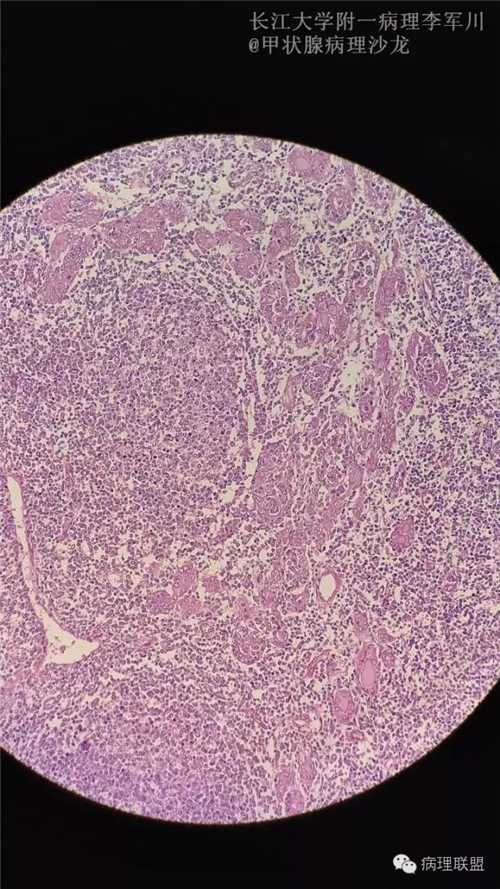

甲状腺病变中的MALT?

女,40余岁,右侧甲状腺肿块,直径约3cm。